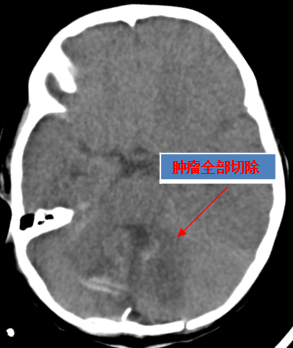

3月29日,神经外科陈陆馗主任团队为小蒙实施“枕下后正中入路第四脑室巨大肿瘤切除术”,手术进行了近9小时后顺利完成,术后小蒙被送往ICU进行监护。

“从ICU出来后,小蒙转到神经外科重症监护病房,已经可以完全独立进食、喝奶,肢体活动也恢复正常,和父母有一定的交流。4月16日,小蒙已顺利出院。接下来要进行全身化疗,预防肿瘤细胞在中枢神经系统包括脑和脊髓的扩散” 陈陆馗说。